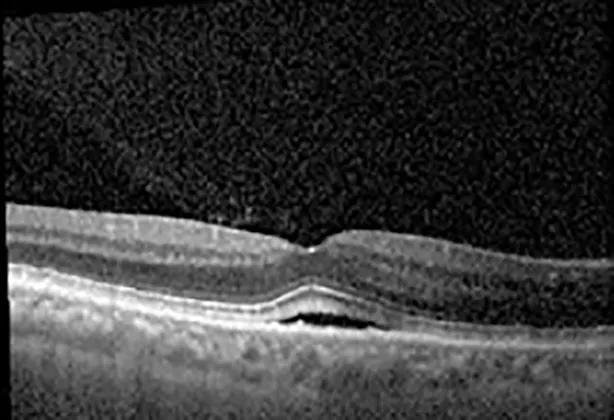

The patient began treatment with oral pemigatinib daily and was followed up for an ophthalmic examination during the second treatment cycle approximately 5 weeks into the treatment process. The patient had at this stage received 28 doses of 13.5 mg per day, which was administered in cycles of 14 on-days and 7 off-days, and had no visual or ophthalmic complaints. The non-corrected VA was OD 20/30 + 1 and OS 20/20. The OCT examinations revealed subfoveal SRF bilaterally. The fundus examination was otherwise unremarkable outside the patient’s prior documented peripheral drusen. Repeat autofluorescence was overall unchanged, though a slight hypofluorescent ring may be visualized in Figure 2. The current pemigatinib protocol recommendation for asymptomatic patients suggests no dose modification; however, with worsening presentation or positive symptoms, it is recommended to withhold pemigatinib. After discussion with the patient’s oncologist, it was decided to continue the medication at this time. Serial monitoring of the patient’s symptoms, vision, and SRF were conducted on specific days during active treatment cycles and days off-cycle to monitor the SRF. Subsequent evaluations demonstrated complete resolution of SRF while off-cycle, and asymptomatic re-accumulation of fluid while on-cycle with varying levels of VA. (Table 1) As we see demonstrated in the table below, in the later stages of the active cycles, such as day 13 of 14 of cycle 2, day 13 of 14 of cycle 3, day 13 of 14 of cycle 4, and day 14 of 14 on cycle 5, the patient’s VA showed no correlative changes based on the presence of SRF. The fluctuations in the patient’s VA certainly occurred, but were likely to be secondary to surface changes, as certain off-cycle days actually presented with lower acuities than days when the SRF was present on OCT examination.

Table 1

| Cycle, day, on/off | VA OD; OS | CMT OD; OS | OCT OD | OCT OS |

|---|---|---|---|---|

| Prior to initiation | 20/40; 20/20−2 | 274; 275 | ![]() | ![]() |

| Cycle 2, day 13/14, on | 20/30+1; 20/20 | 365; 355 | ![]() | ![]() |

| Cycle 2, day 4, off | 20/30−2; 20/20−2 | 282; 280 | ![]() | ![]() |

| Cycle 3, day 6/14, on | 20/40−1; 20/30−1 | 306; 301 | ![]() | ![]() |

| Cycle 3 day 13/14, Oon | 20/50+1; 20/30−2 | Poor tracing; 376 | ![]() | ![]() |

| Cycle 3, day 3, off | 20/30−1; 20/25 | 320; 329 | ![]() | ![]() |

| Cycle 3, day 10, off | 20/50−2; 20/30−1 | 269; 276 | ![]() | ![]() |

| Cycle 4, day 8/14, on | 20/50−2; 20/30 | 333; 317 | ![]() | ![]() |

| Cycle 4, day 13/14, on | 20/40−2; 20/25 | 360; 348 | ![]() | ![]() |

| Cycle 4, day 1, off (9/6) | 20/30; 20/25−1 | 273; 271 | ![]() | ![]() |

| Cycle 5, day 14/14, on | 20/30−1; 20/20 | 375; 364 | ![]() | ![]() |

| Cycle 5, day 6, off | 20/40+2; 20/30−2 | 276; 278 | ![]() | ![]() |

Highlights the visual acuity, central macular thickness, and the physical OCT of the macula for this patient in both the right and left eyes during various stages of the patient's chemotherapy treatment cycle.